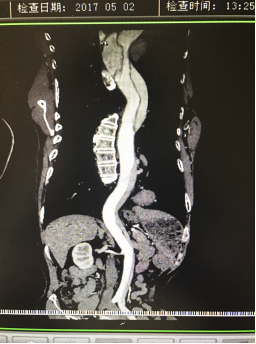

5月2號劉大伯照常早起干活,突然胸部劇烈疼痛,難以忍受,全身大汗,同時伴有右上肢發(fā)涼,他心想這次心絞痛比之前嚴(yán)重的多啊,趕緊叫上孩子到吉林國文醫(yī)院心血管內(nèi)科住院,患者長期高血壓病史,血壓一直控制不理想,大夫給他做了檢查,測左上肢血壓:82/45mmHg,右上肢血壓測不出,心率52次/分,右側(cè)肱動脈、尺動脈、橈動脈搏動消失,左側(cè)股動脈搏動較右側(cè)弱?!霸懔?,雙側(cè)血壓差別這么大,是不是主動脈夾層了?”,接診大夫趕緊找來李主任,李主任反復(fù)詢問患者病情,表情突然凝重起來,患者胸痛這么明顯,血壓低的厲害,主動脈夾層的可能性很大。二話不說,李主任立即聯(lián)系影像科的醫(yī)生準(zhǔn)備做主動脈CTA,移動患者做檢查的過程大夫們非常小心,嚴(yán)密監(jiān)測患者血壓變化情況。兩個小時后結(jié)果出來了,主動脈夾層從升主動脈一直撕裂到左側(cè)髂總動脈!??!